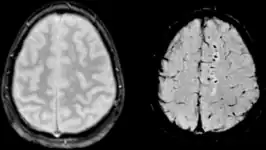

Beeldvorming

Op een CT-scan zal men meestal geen afwijkingen zien. Op MRI-beelden is de kans groter om afwijkingen te zien. Omwille van praktische redenen zal men evenwel na een ongeval meestal een CT-scan uitvoeren en pas (veel) later, indien klachten aanhouden of indien één of meerdere nieuwe ernstige neurologische klachten verschijnen, overgaan tot een uitvoeren van een MRI. Komen er MRI-letsels voor bij een voorheen gezond mens dan is het vrijwel zeker dat de vastgestelde letsels door het ongeval veroorzaakt werden indien er voor deze letsels geen andere verklaring is. Het valt regelmatig voor dat er DAI is terwijl noch CT, noch MRI dergelijke hersenbeschadigingen kunnen detecteren.